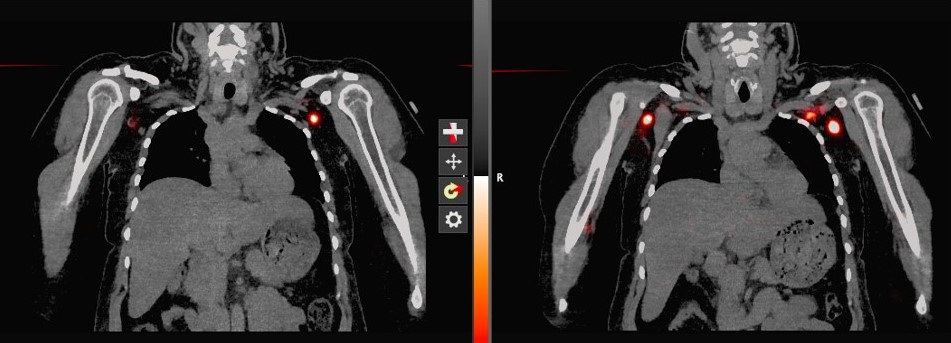

SPECT CT

SPECT/CT Lymphoscintigraphy:  SPECT/CT stands for single-photon-emission computed tomography. This scan consists of combining a CT scan (which lets us see your anatomy clearly) with a scan that tracks the progression of a tracer through that anatomy over a certain period of time. It lets us see the volunteer's anatomy with clarity as the tracer moves through.